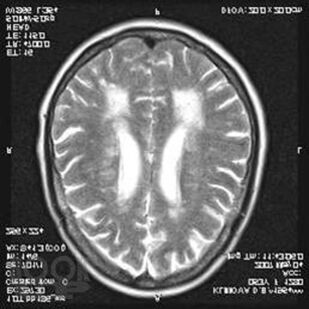

В руководстве представлены сведения о группе дегенеративных заболеваний нервной системы, встречающихся в клинической практике врача-невролога. Обсуждаются современные данные по эпидемиологии, этиологии, патогенезу, клинической картине, диагностике, дифференциальной диагностике, лечению и прогнозу.